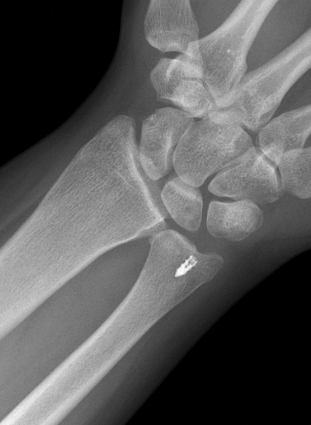

Ulna styloid process fracture and acute DRUJ instability

Ulna styloid fracture with TFCC injury

Isolated ulna styloid fractures with DRUJ instability

Classification ulna styloid process fractures

| Type 1: Tip fracture | Type 2: Base fracture |

DRUJ potentially unstable |